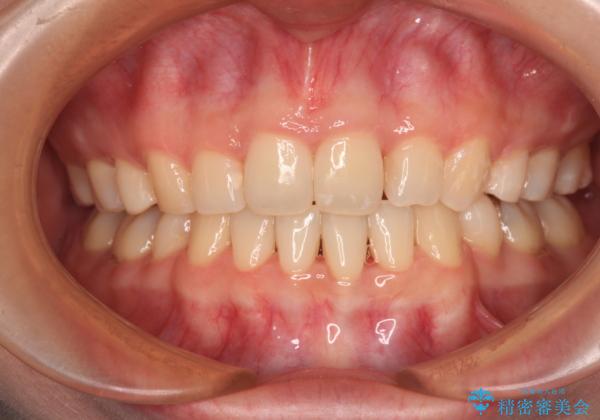

口元の突出感のない、すっきりとした仕上がりとなりました。